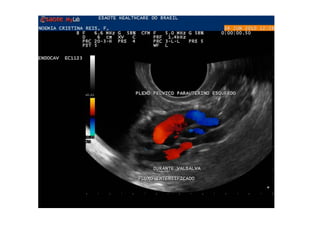

•  Examen  du  cas   d’une  pa=ente   traitée  pour  de   l’endométriose  par   chirurgie,  qui   con=nuait  a  avoir   une  conges=on   pelvienne.  L’examen   a  démontré  qu’elle   souffrait  également   de  varices   pelviennes.

Refluxo  de  veia  Gonadal  com  formação   varicosa  ao  lado  do  ovário

Comment  établir  le  diagnos=que  ?   1.  Par   la   symptomatologie,   en   par8culier   la   douleur  et  la  lourdeur  dans  le  bassin  avec  une   aggrava8on   pendant   la   menstrua8on,   mais   aussi   la   dysménorrhée,   la   dyspareunie,   la   cons8pa8on  et  les  douleurs  lombaires.   2.  Par   la   présence   de   varices   dans   la   région   postérieure   et   latérale   des   cuisses,   dans   les   fessiers  et  les  par=es  génitales.   3.  À   l’aide   d’un   écho-­‐doppler   transvaginal   et   abdominal.